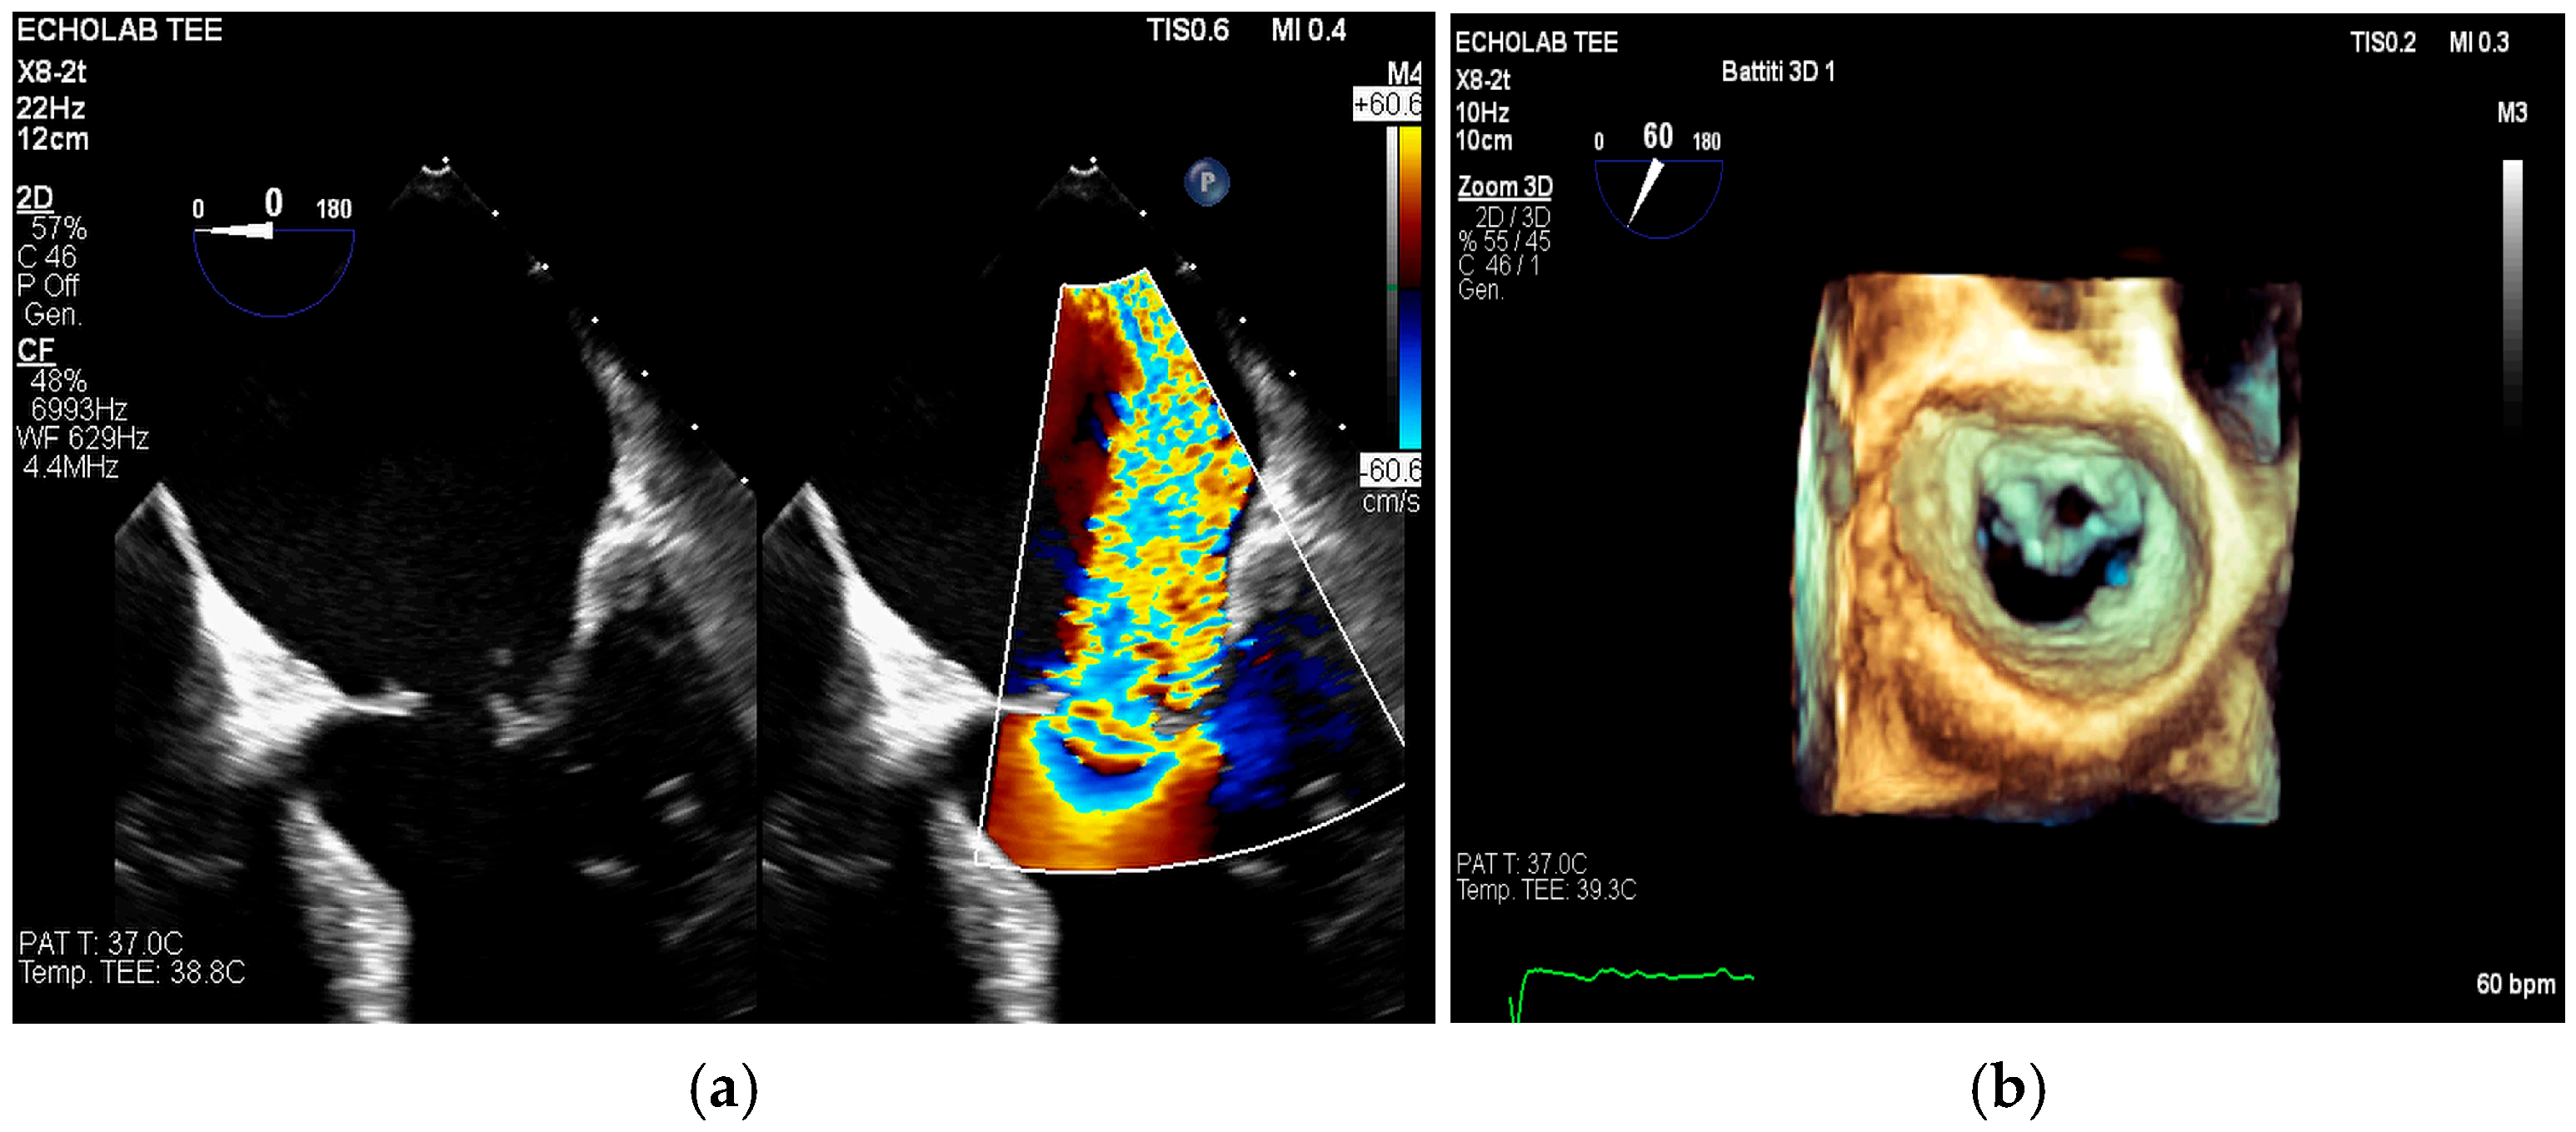

- intracardiac fistula, visualized as an abnormal communication between cardiac chambers or vessels, is often detected by using color Doppler.

- significant new valvular regurgitation compared with previous imaging, i.e., increase in regurgitant jet size, vena contracta width…